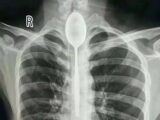

マリーさんは13歳の時、ひどい咳の発作に見舞われ、病院に担ぎ込まれた。レントゲンの結果、声帯に異常なし。気管支炎と喉頭炎と診断されて治療を始めたが、一向に良くなる気配がない。それきり、まったく声が出せなくなってしまったという。

専門家の調べで、このコインが彼女の声帯に挟まり、発声するための振動を邪魔していたことが判明。運悪く、コインは喉の内壁に水平に着地していたため、レントゲンで見落とされたらしい。